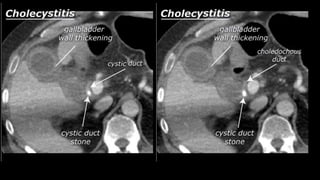

• Cholecystitis

• A complication of bile stones is an infected

gallbladder or cholecystitis. Cholecystitis

rarely occurs in the absence of bile stones.

Ultrasound is also best suited to diagnose

cholecystitis. Ultrasound improves the

visibility of the bile stones, and gallbladder

compressibility can be evaluated (dynamic

examination). Absent compressibility

constitutes a key characteristic of

cholecystitis (see abdominal ultrasound

class). Other characteristics of cholecystitis

on CT include gallbladder wall thickening

and infiltration of the fat surrounding the

gallbladder. A common complication of

cholecystitis is gallbladder perforation,

where bile leaks into the abdominal cavity

(biloma).

• Cholecystitis • Acomplication of bile stones is an infected gallbladder or cholecystitis. Cholecystitis rarely occurs in the absence of bile stones. Ultrasound is also best suited to diagnose cholecystitis. Ultrasound improves the visibility of the bile stones, and gallbladder compressibility can be evaluated (dynamic examination). Absent compressibility constitutes a key characteristic of cholecystitis (see abdominal ultrasound class). Other characteristics of cholecystitis on CT include gallbladder wall thickening and infiltration of the fat surrounding the gallbladder. A common complication of cholecystitis is gallbladder perforation, where bile leaks into the abdominal cavity (biloma).